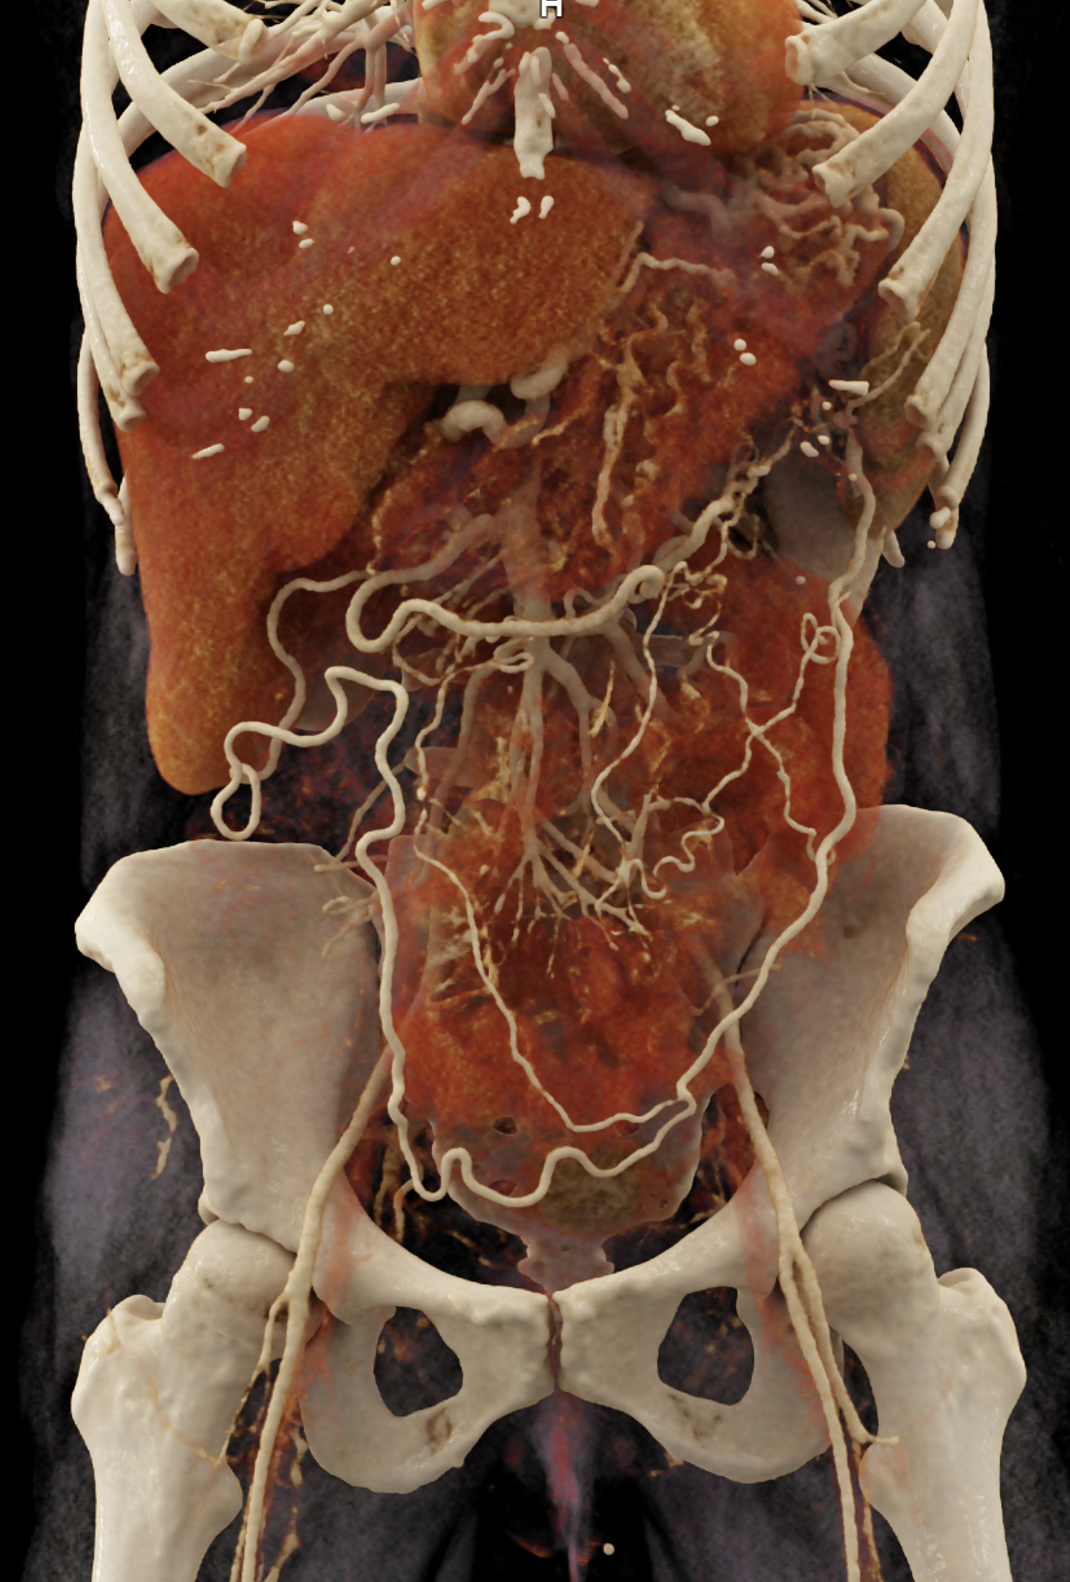

A patient with chronic pancreatitis and chronically occluded portal vein. The bile ducts have a significantly dilated wall, from the trunk, through the stump of the cystic duct, to the right and especially the left branch of the hepatic duct. At the same time, a large pseudocyst in the pancreas, dilatation of the pancreatic duct, and chromic occlusion of the superior mesenteric vein, splenic vein, and portal vein trunk are evident. Along with portal biliopathy, there is also arixy of the cardia and esophagus, as well as cavernous remodeling of the portal circulation itself.

volume rendered image after bone removal